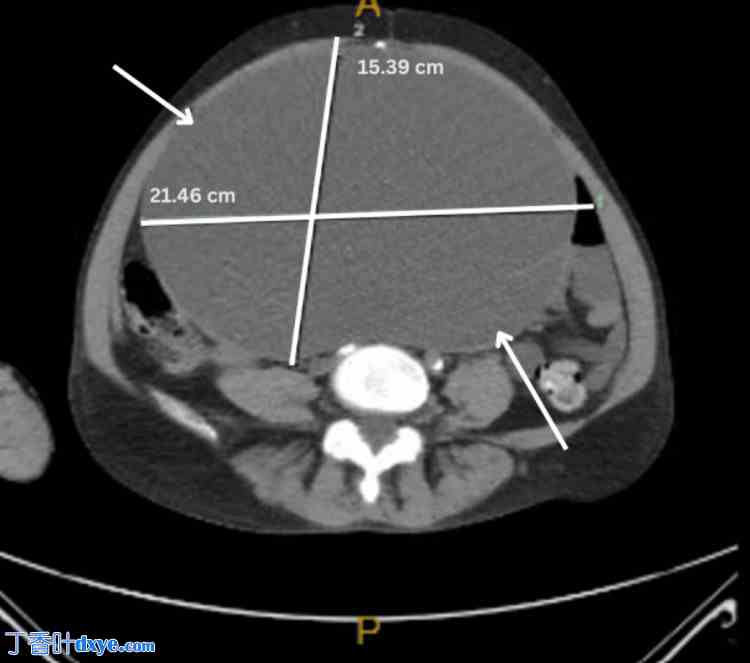

图 2. 右侧边缘性卵巢肿瘤的横断面 MRI 图像,大小为 21.46 cm x 15.39 cm。

2.jpg